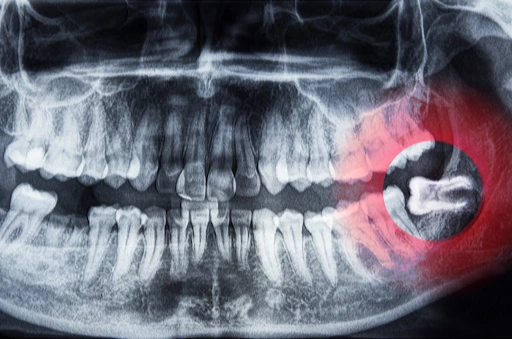

Dersom du opplever slike symptomer, bør du oppsøke tannlegen for en vurdering. I noen tilfeller kan det være nødvendig med en røntgenundersøkelse for å se hvordan visdomstennene ligger i kjeven. Ofte vil tannlegen anbefale å fjerne visdomstann før den skaper større problemer.

Måten en visdomstann fjernes på, avhenger av hvordan den ligger. Dersom tannen er brutt helt frem og står rett, kan det være mulig å trekke den relativt enkelt hos tannlegen. Hvis tannen ligger delvis eller helt dekket av tannkjøtt eller ben, kan det være nødvendig med kirurgisk fjerning.